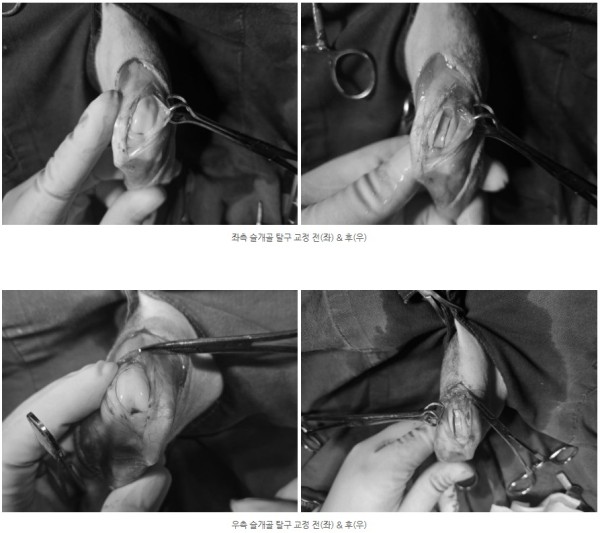

양쪽 모두 안쪽으로 슬개골이 빠지는 내측탈구 4기 상태가 확인되었고

통증의 근본 원인을 해결하기 위해 양측 모두 슬개골 탈구 교정술(MPL)을 진행하기로 결정하였습니다.